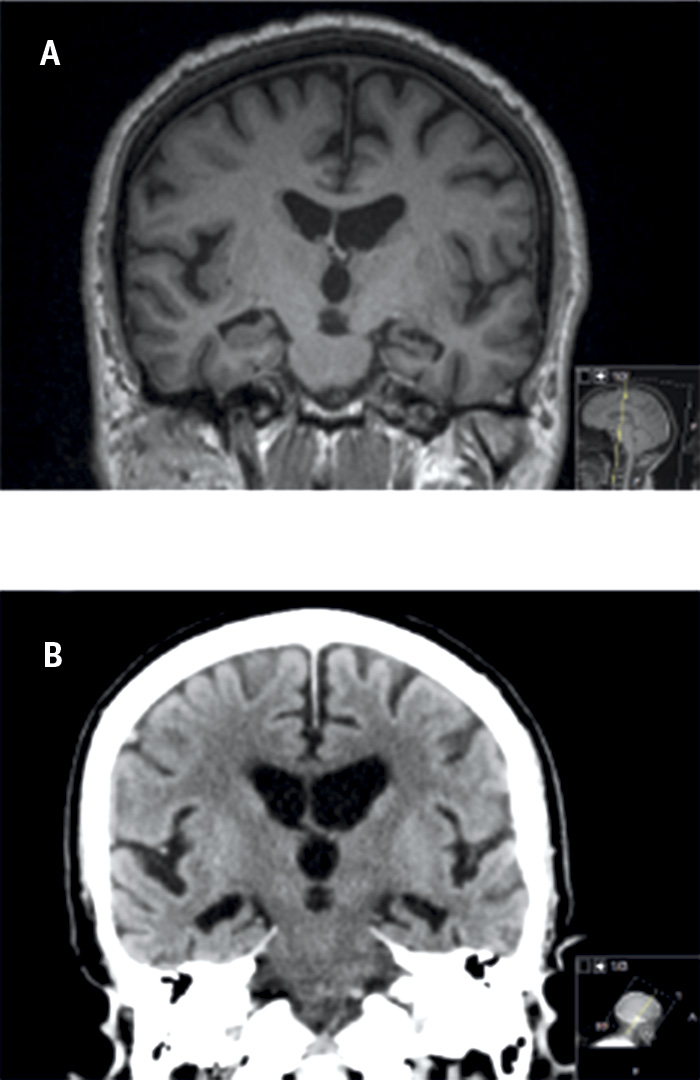

Metoden togs ursprungligen fram för bedömning av MR-bilder men kan även användas för bedömning av medial temporallobsatrofi med dagens DT-teknik och för jämförelse mellan MRT och DT [16] (Figur 2). Resultat från denna metod har visats vara signifikant korrelerade med manuella mätningar av hippocampus [15], och sensitiviteten och specificiteten är jämförbara med automatiska metoder för volymberäkningar och mätning av kortikal tjocklek [17]. När det gäller reliabilitet (intra- och inter-) över tid är den mycket hög för en erfaren bedömare. Dock är reliabiliteten något lägre mellan två bedömare om de inte arbetar tillsammans. Den är också starkt beroende av erfarenhet hos bedömaren [18].

Figur 2. MR från år 2009 (A) och DT från år 2012 (B) på samma patient med diagnosen Alzheimers sjukdom. Notera progress av såväl medial temporallobsatrofi som ventrikeldilatation.